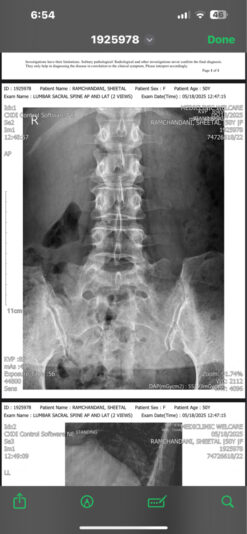

@Bernadette_Abraham my concern at this moment is lower back pain which has been on for a month ,

X-rays say no spine issues , discs or bulge but the lower back pain does not seem to reduce even after physiotherapy sessions , my reports as shared below seem fine as mentioned by the orthopedic doctors

attached is the xray report